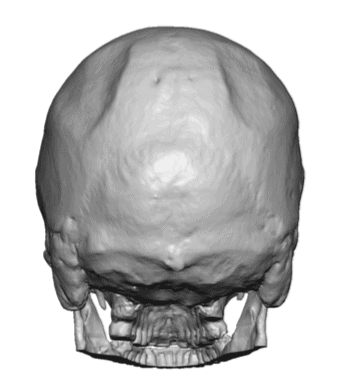

Patient 100

Desire for reshaping of an asymmetric flat back of the head in a shaved head male.

A combined back of the head reshaping procedure was done with a custom skull implant, sagittal ridge reduction and a right temporal muscle reduction.

Desire for reshaping of an asymmetric flat back of the head in a shaved head male.

A combined back of the head reshaping procedure was done with a custom skull implant, sagittal ridge reduction and a right temporal muscle reduction.